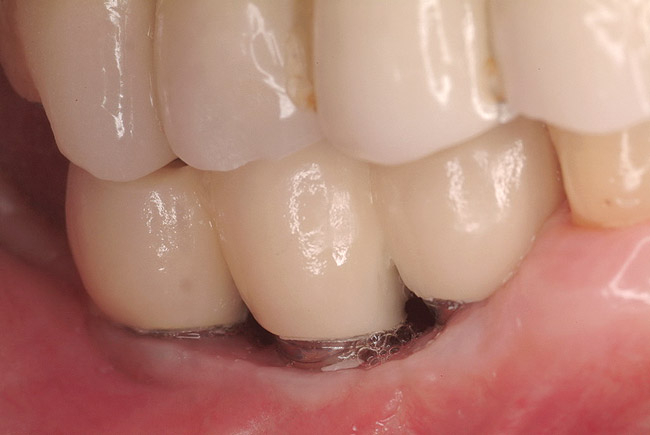

Figure 7  Final restoration of computer-guided implants.

Figure 7